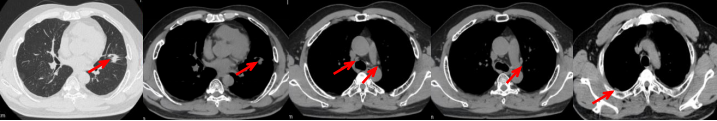

53岁男性,无吸烟饮酒史,脑血栓病史。2024年7月胸部CT:右肺下叶见一团块状软组织密度影,范围约10.8×9.0cm,边界不清,周围并见斑片状磨玻璃密度影,右肺下叶前底段支气管阻塞。纵隔及右肺门见肿大淋巴结影。考虑右肺下叶支气管肺癌。伴纵隔及右肺门淋巴结转移瘤,右下肺静脉瘤栓。2024.7.23行肺穿刺取病理:(肺)腺癌伴有神经内分泌分化。NGS基因检测:RET KIF5B exon15-RET exon12融合。PD-L1(克隆号28-8)TPS=90%。

治疗经过:2024.08开始口服赛普替尼(160mg,bid)。2024.09复查胸CT评效PR。2025.1复查胸CT:右肺下叶外基底段见一不规则形实性肿块,大小约94mm×87mm,边缘呈分叶状,其内密度不匀。右侧胸腔见少许水样密度影。评效PD,PFS=5个月。患者未同意再次组织活检,目前应用卡博替尼治疗,仍在随访中。治疗期间未出现毒性反应。

2024.08

2024.09评效PR

2025.01评效PD